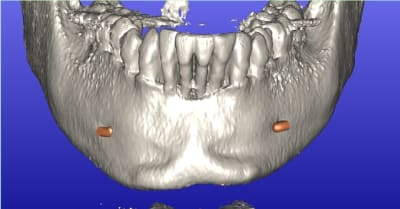

Voilà les images d'un cas de MCI partiel qui je l'espère sera réalisé avant. Cela concerne de 32 à 42 et la 15.

Ce sera j'en sur l’intérêt d'un débat. La question est: Comment faire une extraction implantation immédiate sure reproductible et prévisible; dans une même séance. Évidemment il y aura en même temps un aménagement tissulaire esthétique.